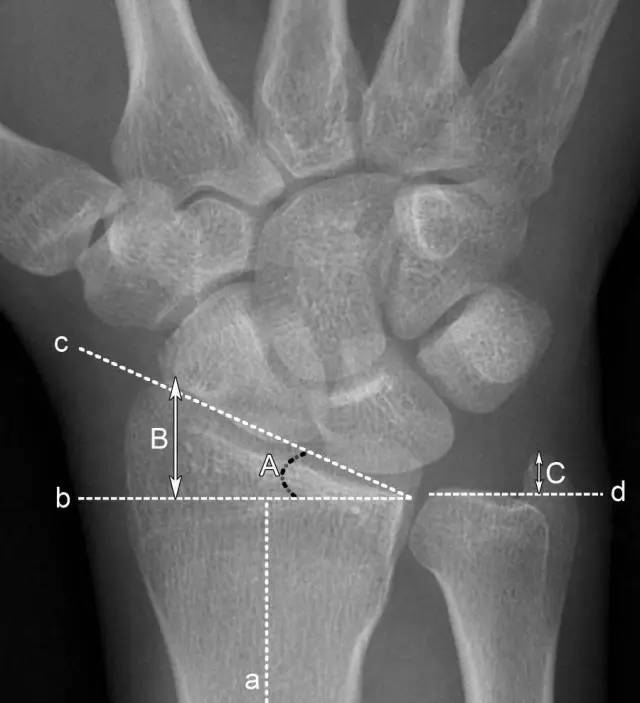

2、腕关节常用测量数据

A.桡骨内倾角:正常为15°-35°。若此角度改变,提示桡骨远端骨折或腕关节脱位;

B.桡骨茎突长度:正常为8-18mm,且桡骨茎突较尺骨茎突低1-1.5cm。若此长度改变,提示桡骨远端骨折;

C.尺骨茎突长度:正常为2-8mm。若此长度改变,提示尺骨茎突骨折或尺骨茎突过长,易引发尺骨茎突撞击综合征。

a.桡骨纵轴线 b.桡骨纵轴线垂线 c.桡骨远端关节面切线 d.尺骨远端关节面水平线 A.桡骨内倾角 B.桡骨茎突长度 C.尺骨茎突长度